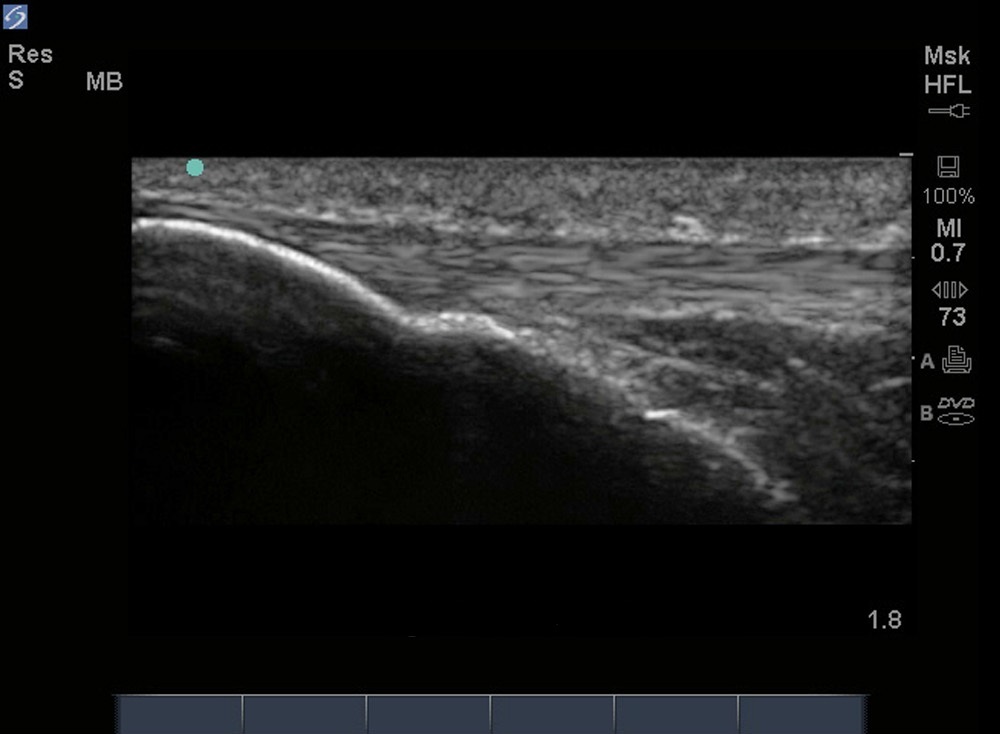

膝矢状膝蓋腱画像